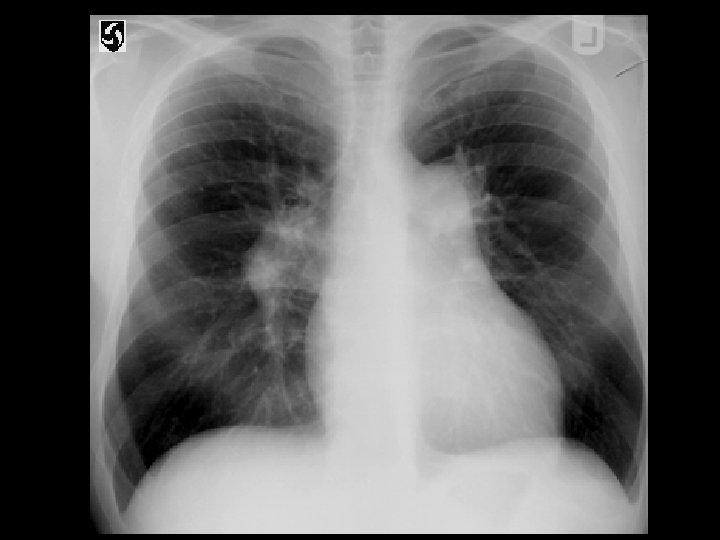

Cryptogenic organizing pneumonia (COP) • Findings: – patchy air-space consolidation in a predominantly peripheral and subpleural distribution • Unknown cause, assoc/w – connective tissue d/o – cocaine/drugs – HIV – MDS • ddx: – Chronic esosinophilic pneumonia – diffuse alveolar hemorrhage